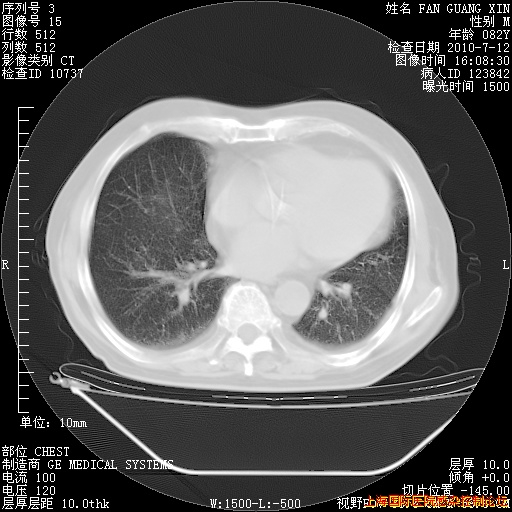

今天复查CT

今天CT

整整相隔30天的肺部CT好像有所好转啊。甲强龙减量第3天,需要观察体温。

海管,自昨日你和我通完话后,不知您岳父消化道症状有无缓解?体温怎样?阅读7.12日胸部ct,个人认为目前激素治疗是有效的,甲强龙减量是适宜的。因在抗痨治疗,需密切观察肝功、肾功能和血常规。不过,老年、长期住院和大量使用激素,很担心菌群失调发生